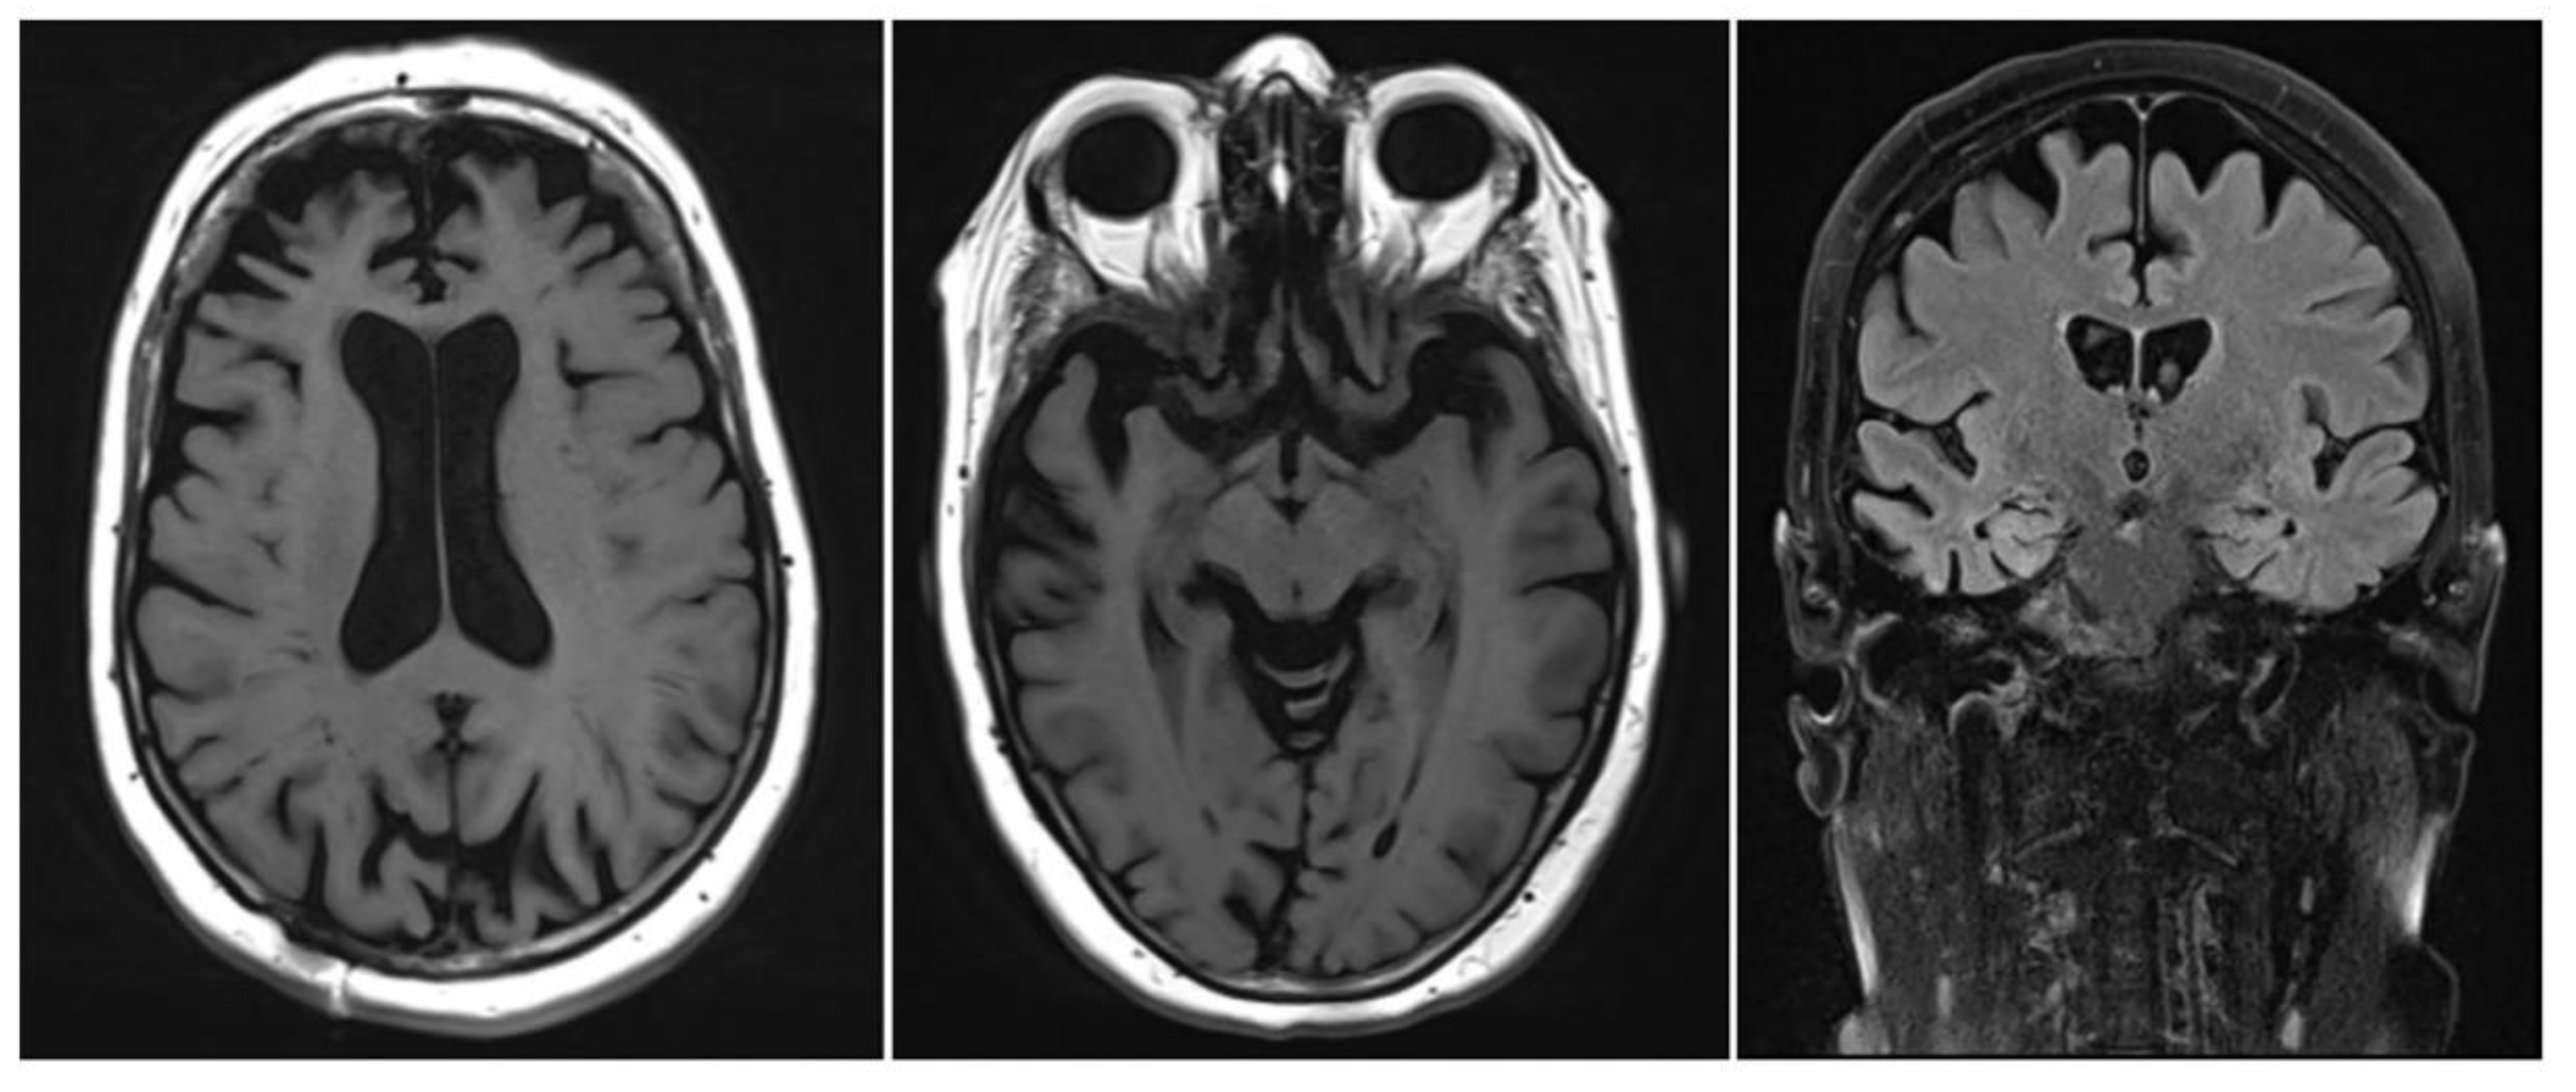

- Chandra, A.; Dervenoulas, G.; Politis, M. Magnetic resonance imaging in Alzheimer's disease and mild cognitive impairment. J. Neurol. 2019, 266, 1293–1302. [Google Scholar] [CrossRef] [PubMed]